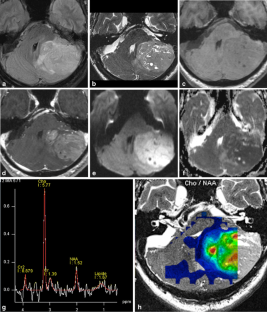

Magnetic resonance imaging spectrum of medulloblastoma

Two medulloblastoma variants were recently added to the WHO classification of CNS tumours. We retrospectively analysed the imaging findings of 37 classic and 27 cases of variant medulloblastomas to identify imaging characteristics that might suggest a particular MB subtype.

Sixty-four patients from three institutions were included. Location, tumour margins, signal intensities on conventional MRI, enhancement pattern, the presence of haemorrhage, calcifications and hydrocephalus were recorded and analysed. Signal characteristics on diffusion-weighted MR images and MR spectra were evaluated when available.

Thirty-seven classic type of MB (CMB), twelve cases of desmoplastic/nodular medulloblastoma (DMB), nine medulloblastomas with extensive nodularity (MB-EN), five cases of anaplastic and one of large-cell medulloblastoma were included. Fifty of 64 tumours were located in the 4th ventricle region. On T2WI, CMB were all hyperintense, whereas DMB and MB-EN showed isointensity in up to 66%. One third of the classic MB showed only subtle marginal or linear enhancement. All medulloblastoma variants showed marked enhancement.

The results of our study suggest: (a) an age-dependent distribution of MB variants, with DMB and MB-EN more common in younger children; (b) a female predominance in DMB; (c) a more common off-midline location in DMB (50%) and MB-EN (33%) variants.

Fig. 3